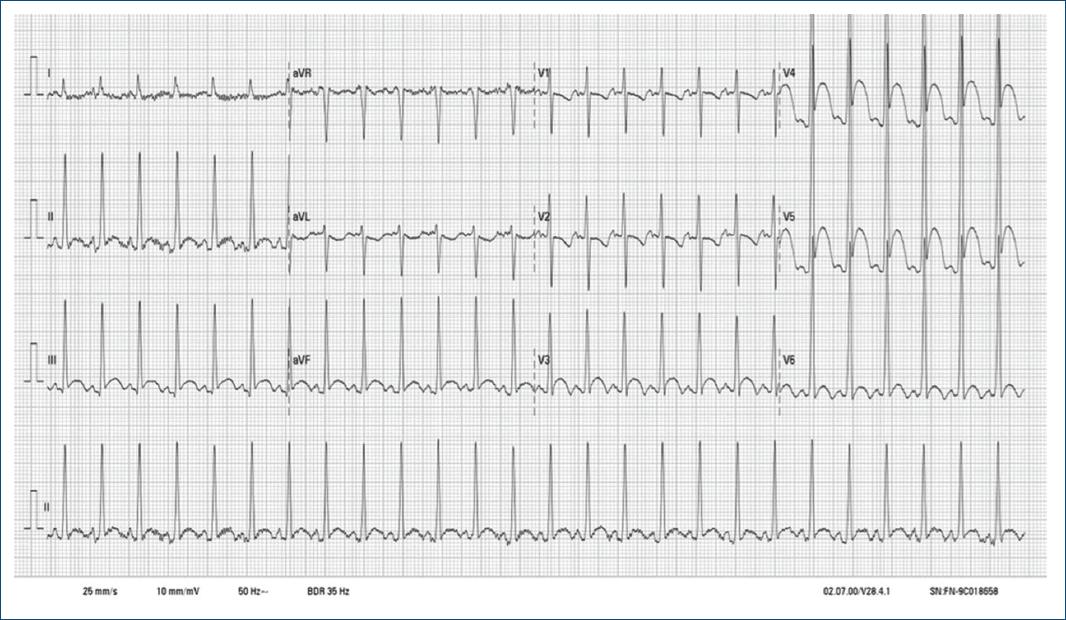

Recién nacida que ingresó para estudio por diagnóstico prenatal de múltiples masas corticales. Se realizó un electrocardiograma que mostró un ascenso del segmento ST en las derivaciones anterolaterales e inferiores, con descenso del ST en las derivaciones I, aVL, V1 y V2 (Fig. 1). El complejo QRS presentaba amplios voltajes, sugestivos de hipertrofia ventricular, sin ondas Q patológicas. Se realizó un ecocardiograma (Fig. 2) que evidenció diversas masas homogéneas hiperecoicas en el tabique interauricular, el ventrículo derecho y el ápex del ventrículo izquierdo, compatibles con rabdomiomas, siendo este último gigante. No presentaba alteraciones de la contractilidad segmentaria y la fracción de eyección estaba preservada. La monitorización continua no registró eventos arrítmicos. El estudio sistémico reveló tuberomas corticales y quistes subependimarios, así como un angiomiolipoma renal, lo que llevó al diagnóstico de complejo de esclerosis tuberosa. La paciente fue manejada de forma conservadora y dada de alta sin incidencias clínicas, programando un seguimiento estrecho multidisciplinario.

La presencia de rabdomiomas es un criterio mayor para el diagnóstico clínico de esta enfermedad; habitualmente son múltiples y con frecuente remisión espontánea1. El electrocardiograma basal suele mostrar alteraciones inespecíficas de la repolarización, siendo eventuales la preexcitación o los trastornos de la conducción2. En el curso clínico se han descrito fenómenos arrítmicos, como extrasistolia ventricular, taquiarritmias supraventriculares o ventriculares y, con menos frecuencia, trastornos avanzados de la conducción3. La elevación manifiesta con patrón regional del segmento ST constituye una manifestación infrecuente.